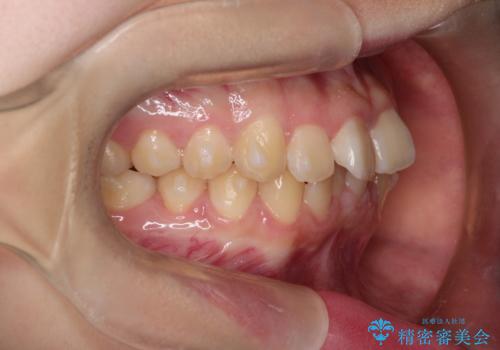

上下の前歯のガタガタを目立たず治したい インビザラインによる見えない矯正

- 上下の前歯のガタガタを治したいとのことで来院されました。

上下の歯と歯の間をわずかに削り、並べる計画としました。

受験生ということもあり、来院頻度が少ないマウスピース矯正で治療が終了できたことに満足いただけました。

上下の正中が一致していませんが、受験を控えているためご本人の希望もあり、いったん終了とさせていただきました。